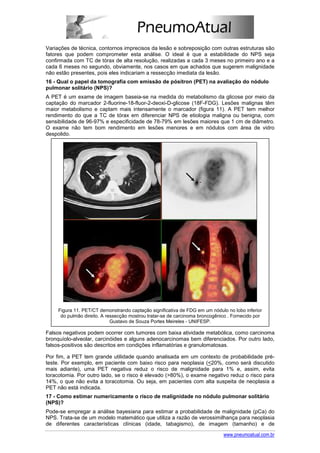

A PET é um exame de imagem baseia-se na medida do metabolismo da glicose por meio da

captação do marcador 2-fluorine-18-fluor-2-deoxi-D-glicose (18F-FDG). Lesões malignas têm

maior metabolismo e captam mais intensamente o marcador (figura 11). A PET tem melhor

rendimento do que a TC de tórax em diferenciar NPS de etiologia maligna ou benigna, com

sensibilidade de 96-97% e especificidade de 78-79% em lesões maiores que 1 cm de diâmetro.

O exame não tem bom rendimento em lesões menores e em nódulos com área de vidro

Figura 11. PET/CT demonstrando captação significativa de FDG em um nódulo no lobo inferior

do pulmão direito. A ressecção mostrou tratar-se de carcinoma broncogênico . Fornecido por

Gustavo de Souza Portes Meireles - UNIFESP.

Falsos negativos podem ocorrer com tumores com baixa atividade metabólica, como carcinoma

bronquíolo-alveolar, carcinóides e alguns adenocarcinomas bem diferenciados. Por outro lado,

falsos-positivos são descritos em condições inflamatórias e granulomatosas.

Por fim, a PET tem grande utilidade quando analisada em um contexto de probabilidade pré-

teste. Por exemplo, em paciente com baixo risco para neoplasia (<20%, como será discutido

mais adiante), uma PET negativa reduz o risco de malignidade para 1% e, assim, evita

toracotomia. Por outro lado, se o risco é elevado (>80%), o exame negativo reduz o risco para

14%, o que não evita a toracotomia. Ou seja, em pacientes com alta suspeita de neoplasia a

PET não está indicada.